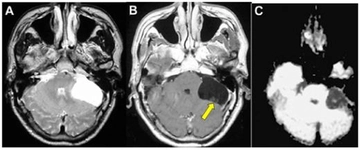

Bu belirtiler, her zaman bir tümörün varlığını göstermez. Ancak, sürekli bir rahatsızlık hissi veya anormal bir değişiklik durumunda, bir sağlık uzmanına başvurmak önemlidir. İyi Huylu Tümörlerin Tanısıİyi huylu tümörlerin tanısı için çeşitli görüntüleme yöntemleri ve biyopsi işlemleri kullanılabilir. Tanı sürecinde kullanılan yaygın yöntemler şunlardır:

Bu yöntemler, tümörün boyutunu, yerini ve yapısını değerlendirmek için kullanılır. Biyopsi, tümörün iyi huylu mu yoksa kötü huylu mu olduğunu belirlemek için kritik bir adımdır. İyi Huylu Tümörlerin Tedavi Yöntemleriİyi huylu tümörlerin tedavi yöntemleri, tümörün büyüklüğüne, yerine ve hastanın genel sağlık durumuna bağlı olarak değişiklik gösterebilir. Tedavi seçenekleri arasında:

Hüsnü bey merhabalar iyi günler dilerim. Kafa dediğiniz kısmı sanırım beyin olarak düşünüyorum. Bu bölgede çıkan tümörler, benign olarak adlandırılan iyi tümörler de olabilir; malign adı verilen kötü huylu tümörler de olabilir. Bunu anlamanın en iyi yolu biyopsi sonucunu beklemektir. Çıkan sonuca göre, doktorunuz uygun bir tedavi planı oluşturacaktır. Sağlıcakla...

Merhaba Hüsnü Bey, meydana gelen kistler kötü huylu da olabilir iyi huylu da. Bu tamamen gelecek olan biyopsi sonucunda karşımıza çıkacaktır. Bu nedenle sabırla beklemekte fayda vardır. Ameliyatlı olan noktanın enfeksiyon kapmaması için şuan buna odaklanıp iyi bir bakım yapmanız tavsiye edilmektedir.